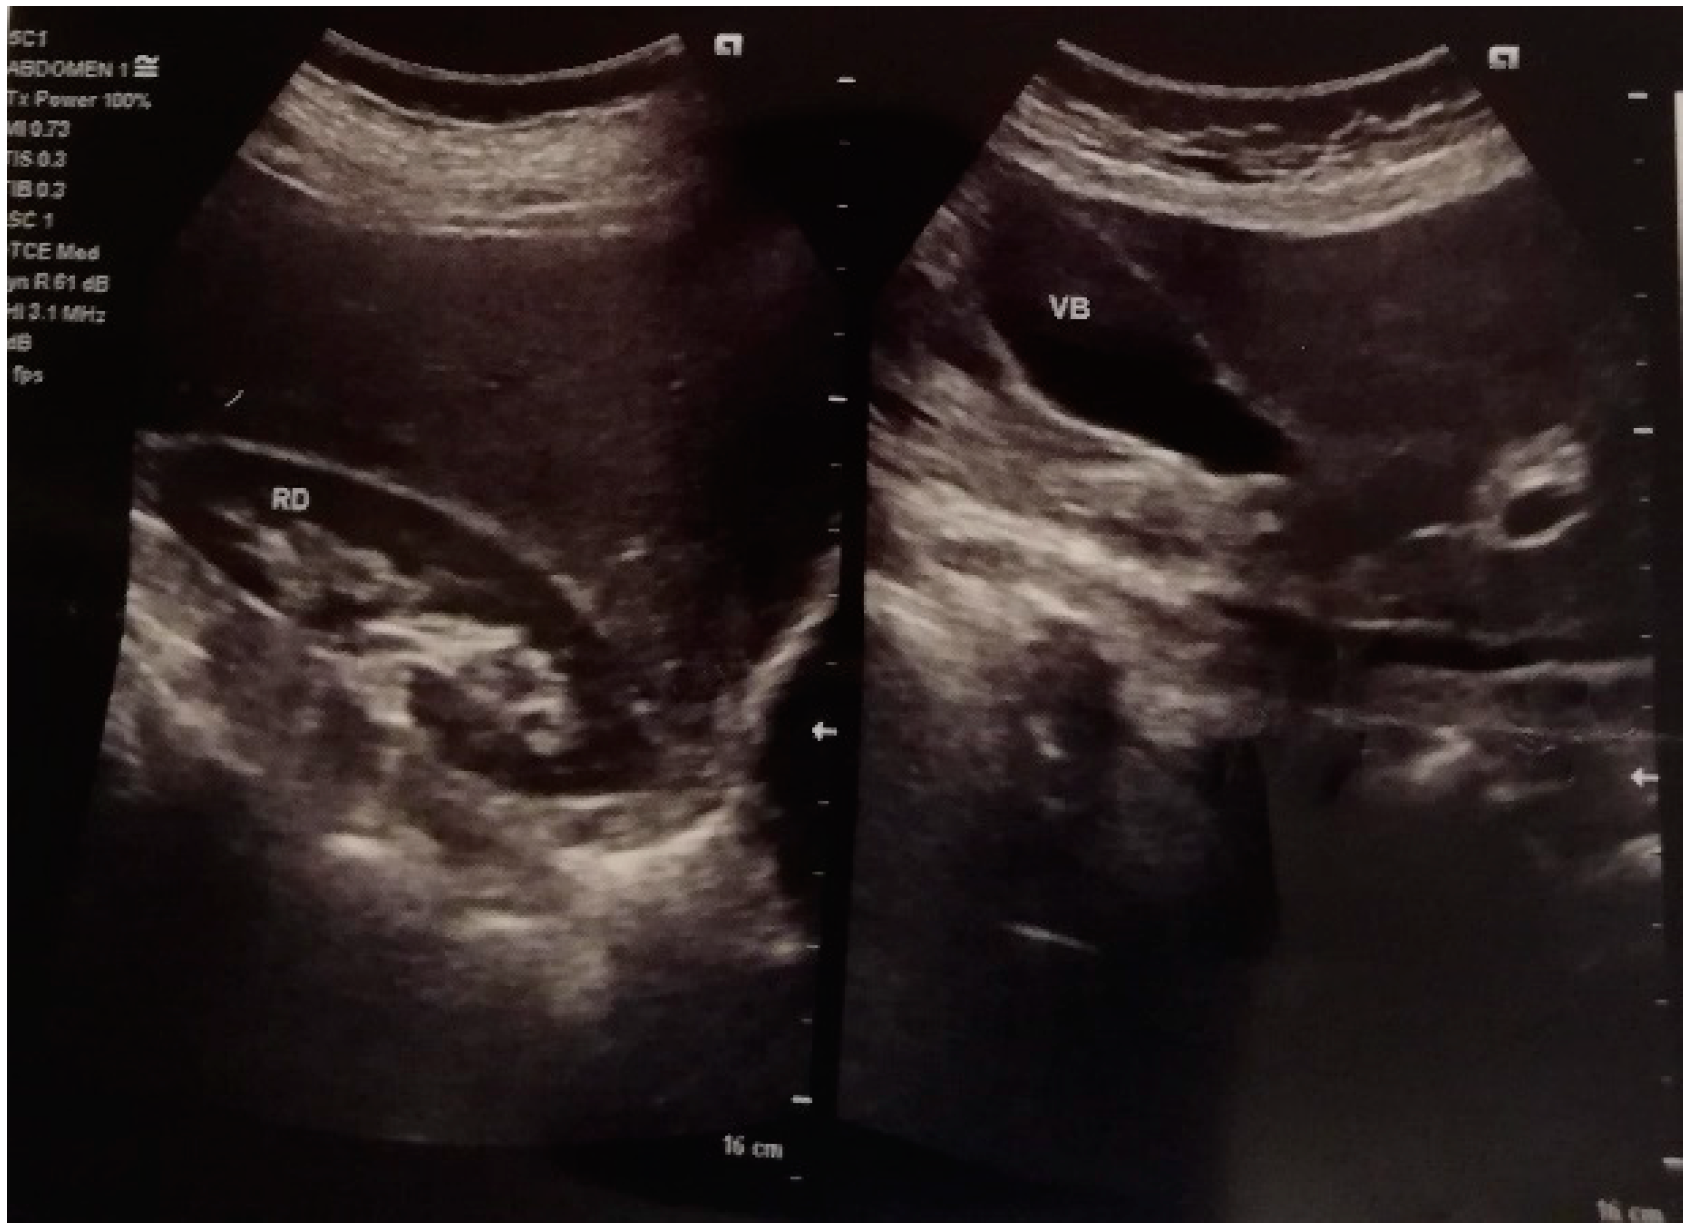

- Gastroenterology exam: normal function, lack of gastrointestinal bleeding, and no hepatic AVM identified.